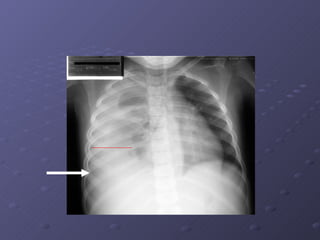

Exames Complementares: Exame Inespecífico: Hemograma completo. Nos casos de forte comprovação: Detecção do Antígeno NS1( FMRP-USP ) RT-PCR para dengue  * Isolamento do vírus. Sorologia Mac-Elisa. Nas complicações: •  Inespecíficos: a) Tipagem sanguínea ; b) Monitorização do hematócrito (2/2 horas); c) Dosagem de eletrólitos séricos e gasometria arterial; d) Contagem de plaquetas, tempo de parcial de tromboplastina e atividade da protrombina; Rx do tórax,Ultrassonografia,dosagem de  albumina, função hepática, função renal e outros exames a depender das complicações.

Complicações: Alterações neurológicas: Tremores, parestesias , hiperestesia cutânea  Diminuição nível de consciência: letargia, agitação, confusão  mental, convulsões  Manifestações psíquicas: Psicose, demência,  amnésia,irritabilidade.  Disfunção cardio-respiratória Insuficiência Hepática Plaquetopenia igual ou inferior a 50.000/mm3  Hemorragia Digestiva  Derrames Cavitários: derrame  pericárdico,pleural ou ascite.